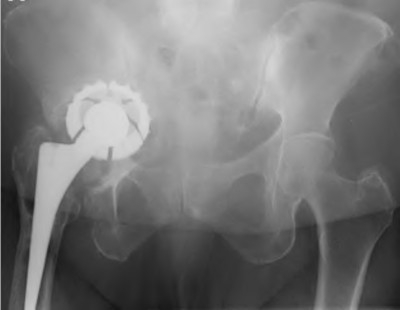

A 75-year-old man underwent total hip arthroplasty 10 years ago. He now reports mild groin pain which has been increasing lately. What is the most likely explanation for the finding in Figure A indicated with the arrows?

Osteolysis of the pelvis is a common complication associated with total hip arthroplasty. Osteolysis affects sockets with and without cement, and has been attributed to the biologic reaction to wear debris. With well-fixed cementless sockets, an expansile pattern of osteolysis is usually seen.

The radiographic appearance has a radiolucent area that starts at the implant-bone interface and expands into the cancellous bone away from the implant.

This pattern of osteolysis can be explained with the concept of effective joint space. This concept states that joint fluid and wear particles will flow according to pressure gradients and follow the path of least resistance.

The Level 5 review article by Chiang discusses osteolysis in further depth.